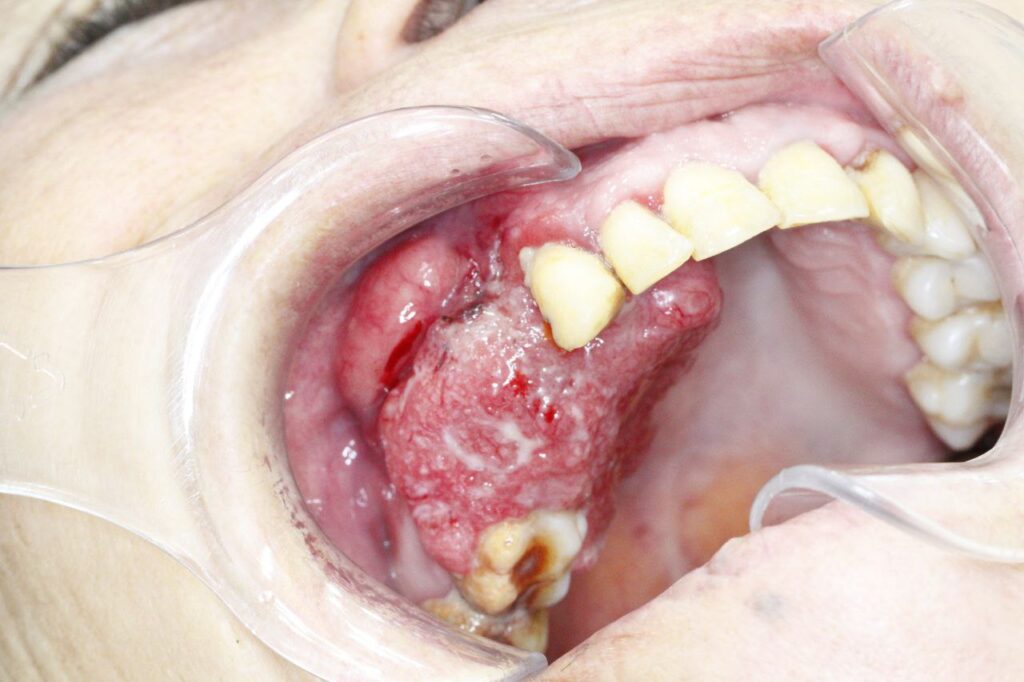

کارسینوم سلول سنگفرشی (SCC):

شایعترین نوع سرطان دهان (بیش از ۹ نفر از هر ۱۰ نفر).

کجاها بیشتر دیده میشود؟ زبان (بهویژه کنارههای زبان)، کف دهان، لثهها، مخاط گونه و کام. در ناحیه لب که مواجهه مزمن با آفتاب در آن نقش دارد.

ضایعات پیش بدخیم یا پیش سرطانی

در اغلب مواقع سرطانهای دهان مانند اسکوآموس سل کارسینوما در ابتدا ضایعات بیآزاری هستند که یا تشخیص داده نشده و یا به درستی مدیریت و درمان نشدهاند؛ این ضایعات در طول زمان دچار تغییراتی شده که درنهایت به یک توده بدخیم تبدیل میشوند. به این ضایعات مانند لکوپلاکیا، اریتروپلاکیا و لیکن پلان دهانی، ضایعات پیش سرطانی گفته میشود. شناسایی زودهنگام و درمان این ضایعات میتواند از بروز بسیاری از سرطانهای دهان جلوگیری کند. متخصصین بیماری های دهان برای معاینات دهانی و تشخیص ضایعات، بهصورت تخصصی آموزش دیدهاند و بهترین گزینه برای غربالگری و تشخیص سرطانهای دهان محسوب میشوند.

دیسپلازی

SCC یا اسکوآموس سل کارسینوما معمولا در یک روند تدریجی ایجاد شده و پیشرفت میکند. این نوع سرطان معمولا از ضایعات پیش بدخیم منشا میگیرد. در مرحله اول ممکن است تنها افزایش لایه شاخی اتفاق افتاده باشد که به صورت یک ضایعه سفید دیده میشود. به مرور تغییرات سلولی نامطلوب در این ضایعات اتفاق میافتد که به این تغییرات دیسپلازی گفته میشود. دیسپلازی بر اساس درجه تغییرات سلولی به خفیف، متوسط و شدید طبقه بندی میشود. در صورتی که درمان به موقع برای این ضایعات از طریق برداشت با جراحی یا لیزر انجام نشود این ضایعات می توانند به سرطان پیشرفته تبدیل شوند.

جراحی

· برداشت تومور با حاشیه سالم پرکاربردترین روش در مراحل اولیه است. جراح فک و صورت بافت سرطانی را همراه با بخش کوچکی از بافت سالم اطراف آن برمیدارد تا احتمال عود به حداقل برسد. هرچه اندازه ضایعه کوچکتر باشد میزان کمتری از بافت برداشته میشود و زیبایی و عملکرد ساختارهای دهانی و صورتی کمتر به خطر میافتد.

بسیاری از افراد آگاه برای انجام معاینات و غربالگری سالانۀ سرطان دهان یا با مشاهدۀ یک ضایعۀ دهانی برای ارزیابی دقیقتر به ما مراجعه میکنند. در مرکز ما ابتدا معاینات کامل و جامع خارجدهانی و داخلدهانی توسط متخصص بیماریهای دهان انجام میشوند. درصورت مشاهدۀ ضایعات مشکوک، اعم از زخمها، ضایعات سفید و قرمز یا برجسته و تودهمانند، از ضایعه نمونهای تهیه شده و برای بررسی میکروسکوپی به مرکز پاتولوژی فرستاده میشود. گاهی اوقات قبل از انجام نمونهبرداری لازم است ناحیه مد نظر با مواد رنگی مخصوصی رنگآمیزی شود تا نواحی مشکوکتر برای نمونهبرداری انتخاب شوند.

بعد از اینکه نتیجۀ پاتولوژی مشخص شد و تشخیص نهایی ضایعه گذاشته شد، بر اساس نوع ضایعه، وجود یا عدم وجود تغییرات سلولی، گسترش سرطان و… دربارۀ مراحل بعدی تصمیمگیری میشود. در این مرحله، گاهی اوقات انجام رادیوگرافیهای تخصصی سر و گردن، مثل سیتیاسکن، امآرآی یا سونوگرافی، ضرورت پیدا میکند. بر اساس نوع ضایعه، گاهی انجام آزمایشات تکمیلی خون نیز درخواست میشود. درصورت تشخیص ضایعات پیشسرطانی، بیمار تحتنظر متخصص بیماریهای دهان قرار گرفته و بهصورت دورهای معاینه میشود تا درصورت مشاهدۀ کوچکترین تغییرات، اقدامات لازم انجام شوند. در برخی موارد، تصمیم به حذف ضایعات با لیزر، فتودینامیک تراپی یا درمانهای دارویی گرفته میشود. اما باید توجه کرد که حتی با حذف تمام ضایعات، معاینات دورهای منظم حتماً باید انجام شوند؛ چراکه احتمال بروز ضایعات مشابه یا سرطان دهان در همان نقطه یا سایر نقاط دهان در این بیماران وجود دارد. درصورت تشخیص سرطان، ضایعۀ دهانی همراه با یک حاشیۀ سالم توسط جراح فک و صورت و معمولاً در بیمارستان برداشته میشود. درخصوص برخی ضایعات بزرگتر که انجام جراحی میتواند باعث از دست رفتن بخش قابل توجهی از بافت دهانی یا عملکرد بیمار شود، پس از مشاوره با انکولوژیست قبل از درمان جراحی، رادیوتراپی یا شیمیدرمانی انجام میشود تا سایز توده کوچکتر شده و برداشت جراحی آن با برداشت بافت کمتری همراه باشد.